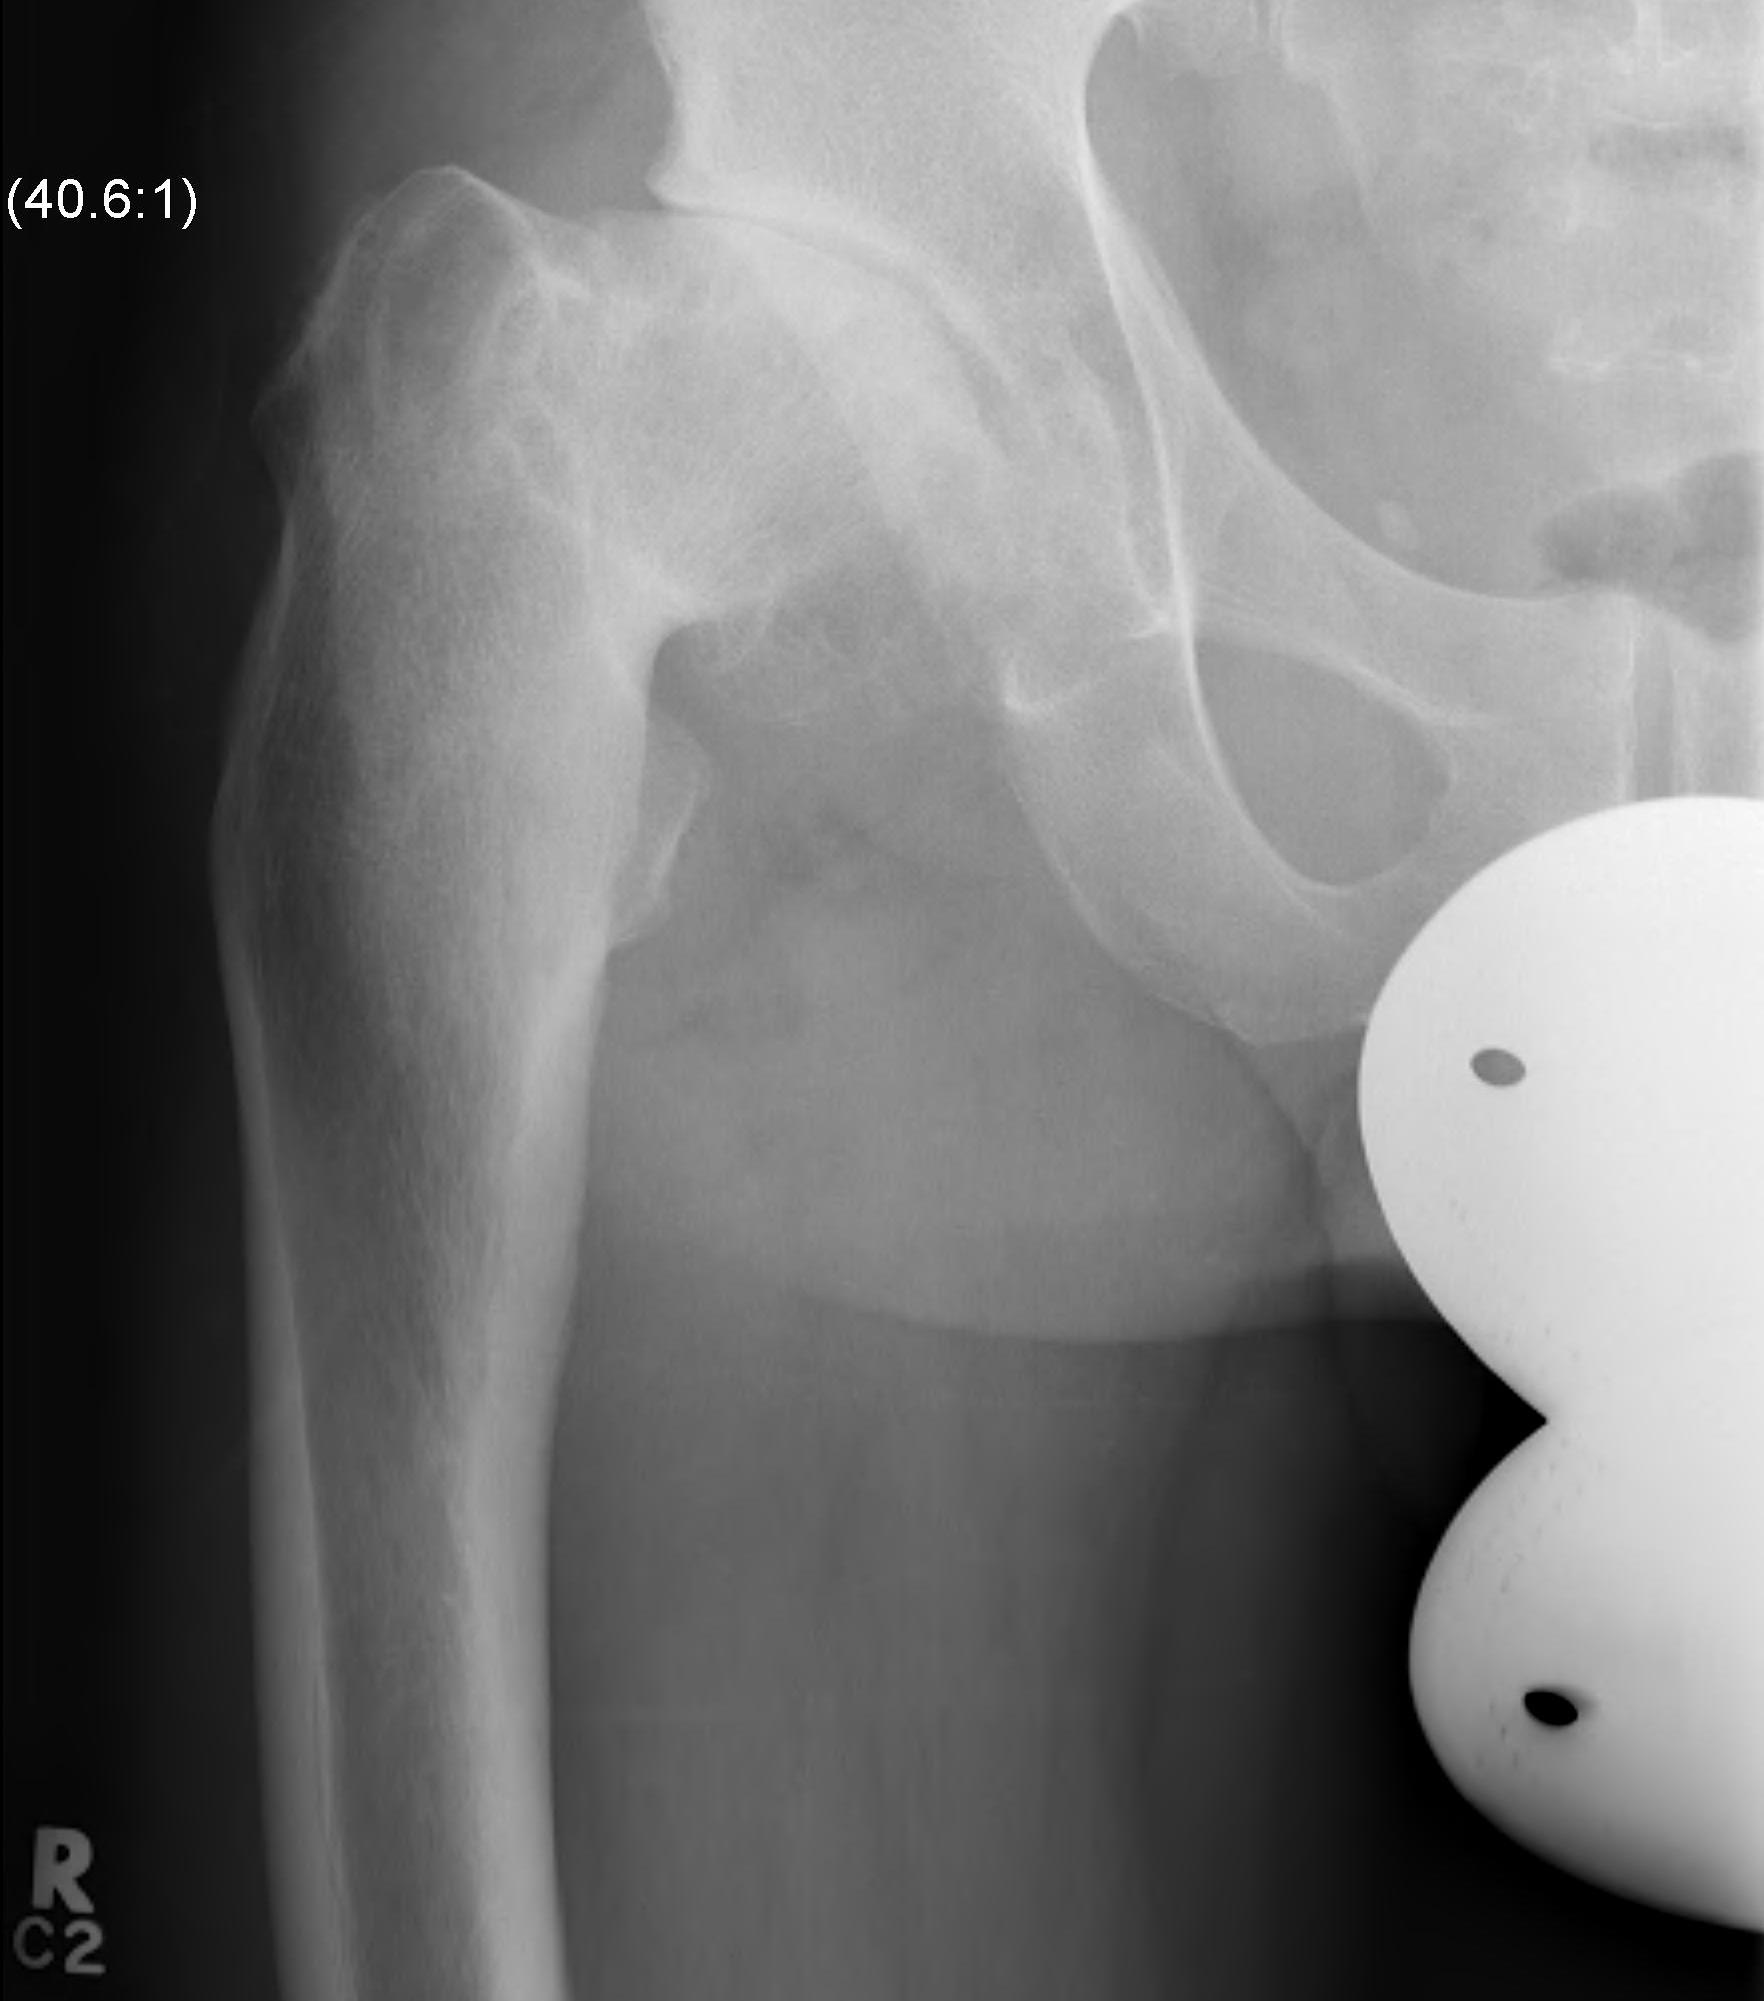

Issues

| Femur | Acetabulum | Leg Length Discrepancy | Abductors |

Multiplanar deformity |

Element dysplasia | 2 - 4 cm | Shortened |

| Worsened by previous surgery | May need trochanteric slide | ||

| Risk of intra-operative fracture | |||

| May require osteotomy |

Shallow acetabulum